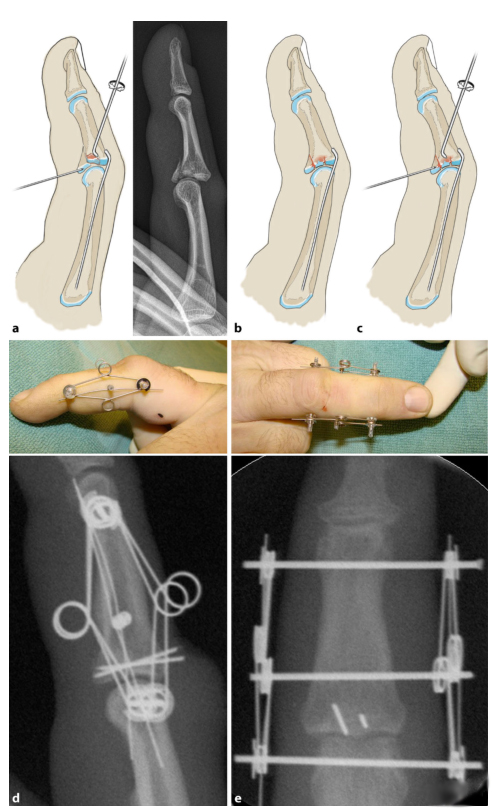

После репозиции через сухожилие сгибателя с ладонной стороны проводили спицу Киршнера диаметром 0,6 мм для фиксации костного фрагмента.

Стальную иглу диаметром 0,4 или 0,6 мм вводят дорсально в ладонный отломок. Ладонную кору необходимо прорвать, но только на несколько миллиметров, чтобы избежать раздражения сухожилий сгибателей.

Наконец, с помощью рентгеноскопии проверяли стабильность проксимального межфалангового сустава (ПМФ) в положении 0°. Соединение PIP должно оставаться стабильным в диапазоне от 20° до 90°. Если сустав PIP все еще имеет тенденцию к подвывиху, необходимо ввести стальной штифт от отведения в костномозговой канал или использовать динамический дистракционный фиксатор (c, d).

Если основание средней фаланги подвывихнуто латерально, сустав вправляется путем тракции и сгибания и удерживается на месте блокирующими спицами. Только после этого можно выполнить операцию сброса.

2) Чем выше нестабильность сустава (например, перелом III типа), тем раньше следует использовать блокирующий штифт. (Как показано ниже)